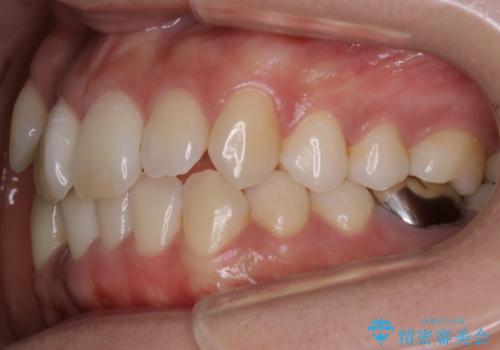

【非抜歯】インビザライン 隠れた前歯を並べる矯正治療

- 前歯のガタつき・奥に隠れてしまっている歯の矯正治療を希望されて初診来院されました。

顔貌的に口元を下げたいといった希望はなく抜歯はなるべく避けたいとのご要望からマウスピース装置(インビザライン)での治療を行うこととなりました。